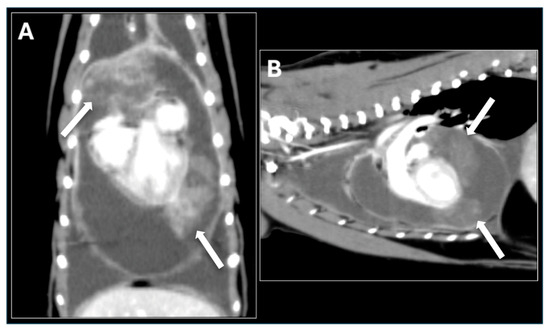

Veterinary cardiology has become a permanent fixture, both in the way of services provided by general practitioners, and also in specialized centers, which are being established in growing numbers around the world. Acquired heart disease, which develops and progresses with age, accounts for the vast majority of cardiac cases. They are also the subject of greatest interest to researchers, due to the prevalence and difficulties encountered during their treatment. Among them, the most common are myxomatous mitral valve disease in small-breed dogs, dilated cardiomyopathy in large-breed dogs and hypertrophic cardiomyopathy in cats. In contrast, congenital heart defects, which are significantly less common, can pose considerable diagnostic challenges and be cumbersome in terms of selecting the optimal treatment protocol. Due to the rapidly developing branch of interventional cardiology, including minimally invasive procedures, a growing number of defects, such as patent ductus arteriosus, pulmonic stenosis, atrial septal defects or ventricular septal defects, can be successfully addressed by surgical methods. In many cases, such treatment results in a complete recovery, which positively affects the rest of the animal's life. With the use of advanced diagnostics, such as 3D and 4D transesophageal echocardiography, cardiac magnetic resonance imaging (MRI), and cardiac computed tomography (CT), the characteristics of acquired and congenital defects and their complexities can be assessed very accurately, favoring the selection of optimal treatment methods, as well as allowing the determination of possible strategies for surgery. Thanks to this comprehensive approach, veterinary cardiology services in many countries around the world have achieved incredibly high standards of care.